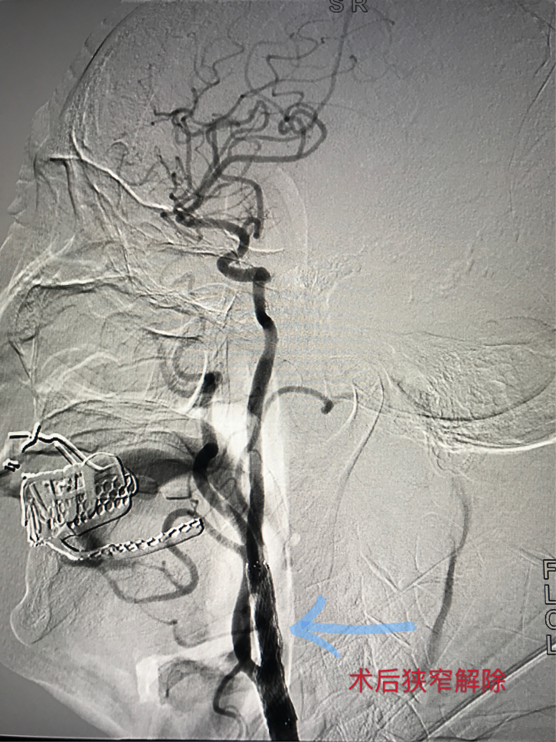

患者男性,73岁,头晕伴四肢无力2年,在我院公共卫生科宣传下,慕名前来我院治疗,9月17日入住神经内科。根据病史、临床表现、颈动脉超声等影像学检查后,发现该患者右侧颈动脉粥样硬化伴斑块形成,右侧颈内动脉重度狭窄,诊断为短暂性脑缺血发作(频发)、脑梗塞、多发脑血管狭窄。由于病情复杂,情况严重,神经内科立即组织病例讨论,最终决定对患者实施介入手术治疗。在完善各项术前检查及准备工作,排除介入诊疗禁忌并征得家属同意后,于9月25日为患者在局麻下行右侧颈内动脉支架成形术,术中造影显示右颈内动脉C1段管腔重度狭窄,狭窄度达95%。随后针对病变血管行血管腔内支架成形术,手术顺利,获得成功。术后造影复查显示血流通畅,狭窄解除。但术后患者心率、血压下降,考虑颈内动脉支架术后影响压力感受器所致,随即转入ICU观察治疗,目前患者状态良好,家属表示很满意。